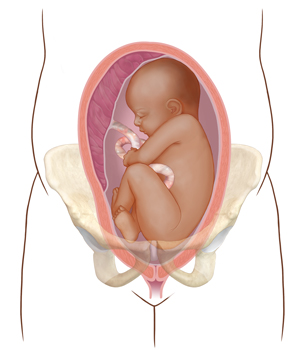

A poor fit. The baby’s head is poorly positioned or too large. This may prevent the baby from fitting through the birth canal.

|

| Poor fit |